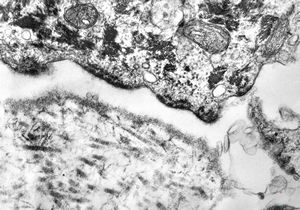

M, 48y. | multiplication of dermal perivascular basement membranes (unclassified myopathy)